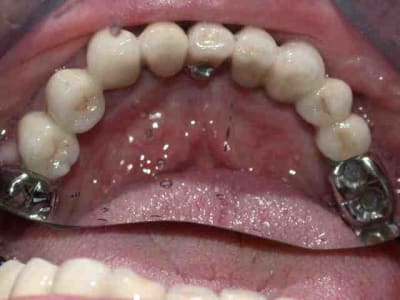

on évoluera par étapes :

1)mise en pace de 3 implants 35 36 37

2) on garde 34 pour stabiliser l'appareil

3)on attend l'ostéointégration des implants.

pano après